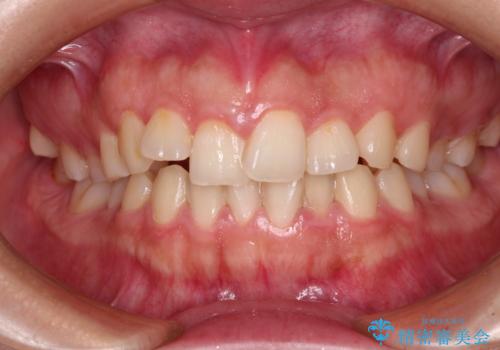

捻れて前に出ている前歯 ワイヤー装置での非抜歯矯正